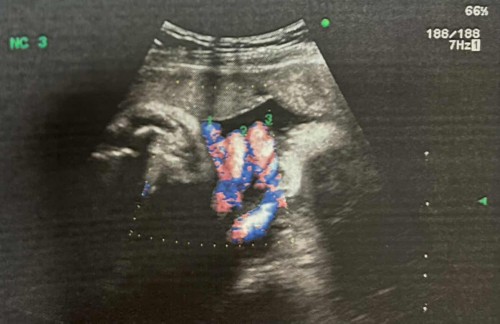

สายสะดือพันคอ3รอบ

ตอนนี้ตั้งท้องน้องได้32weeksแล้ว คุณหมอบอกสายสะดือพันคอ3รอบ ส่วนตัวเราเป็นคนท้องเล็ก แต่น้องน้ำหนักตามเกณฑ์ค่ะน้ำคร่ำปกติ เราก็กังวลว่าน้องจะดิ้นจนหลุดเองได้ไหมเพราะพื้นที่มันน้อยขึ้นทุกวันๆ มีคุณแม่ท่านไหนเคยเจอเหตุการณ์แบบนี้บ้างไหมคะ ขอคำแนะนำหน่อยค่ะ เรากังวลมากๆเลย #ขอบคุณสำหรับคำตอบค่ะ

โอกาสดิ้นหลุดมีน้อยค่ะ แม่ค่อยนับและสังเกตลูกดิ้นอย่างเดียวเลย ถ้ารู้สึกว่าดิ้นน้อยผิดสังเกตรีบไป รพ ติดเครื่องดูอัตราการเต้นหัวใจน้องเลยค่ะ

โอกาสที่จะดิ้นแล้วหลุดเองนะน้อยมากๆเลยค่ะแม่เพราะว่าพื้นที่เหลือน้อยแล้ว (บ้านนี้พัน2รอบ) ต้องสังเกตุการดิ้นดีๆนะคะ